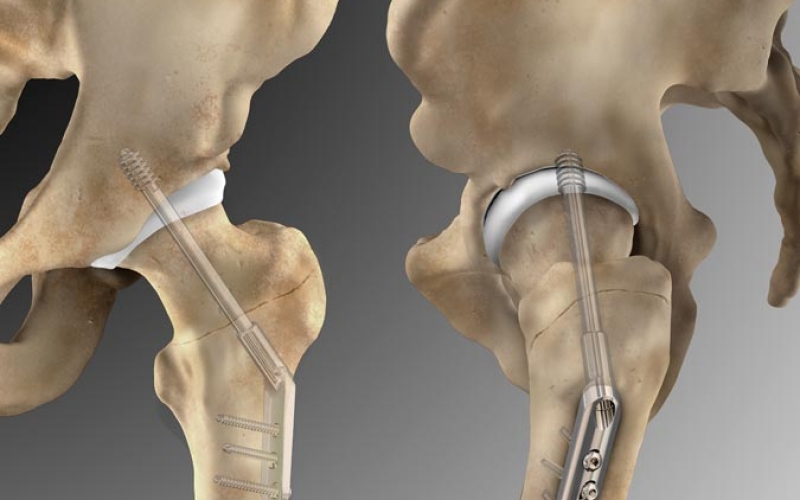

In this illustration we see the Omega3 Compression Hip Screw System used to repair a fractured femur. You are looking at both the anterior view (left) and the lateral view on the right. The injury illustration can be seen here.